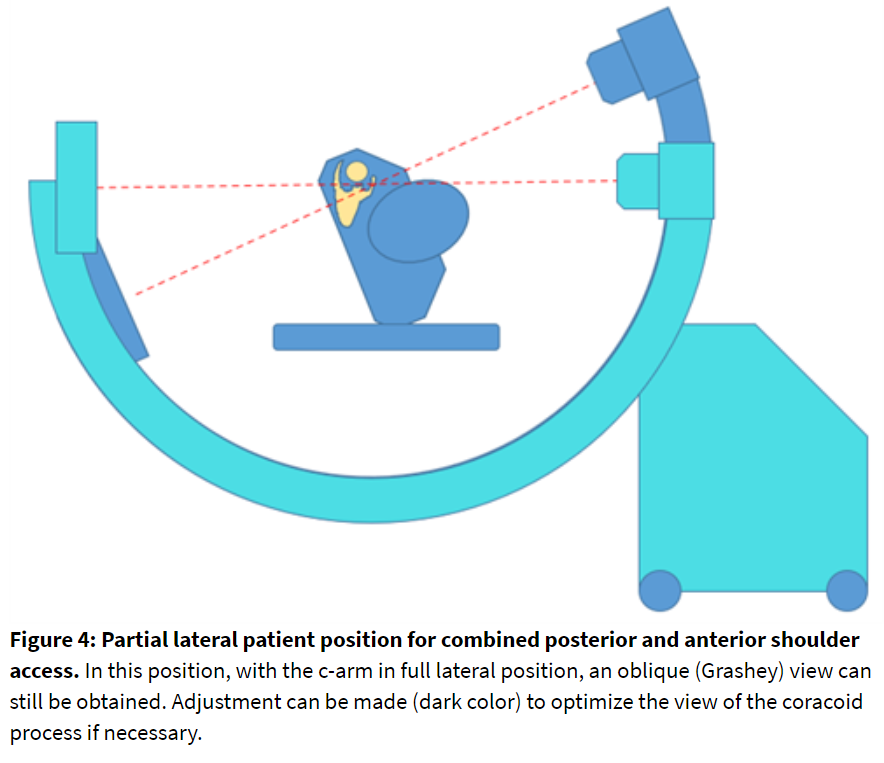

Alternate Position: Partial Lateral

Assuming both anterior and posterior nerves need to be blocked, the patient can be positioned in the lateral decubitus position. A partial lateral position (Figure 4) can provide proper joint visualization with fluoroscopy. The C-arm orientation should be evaluated in advance. Image acquisition and needle stabilization guidance can be more challenging in this position when compared to the staged prone-supine technique.